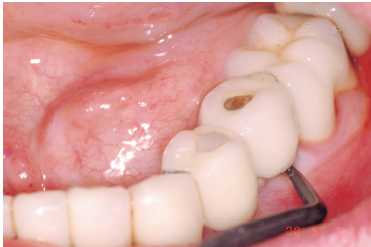

Figuras 2a y 2b. Adiestramiento en la clínica con el

paciente de la utilización de superflos y cepillos interproximales